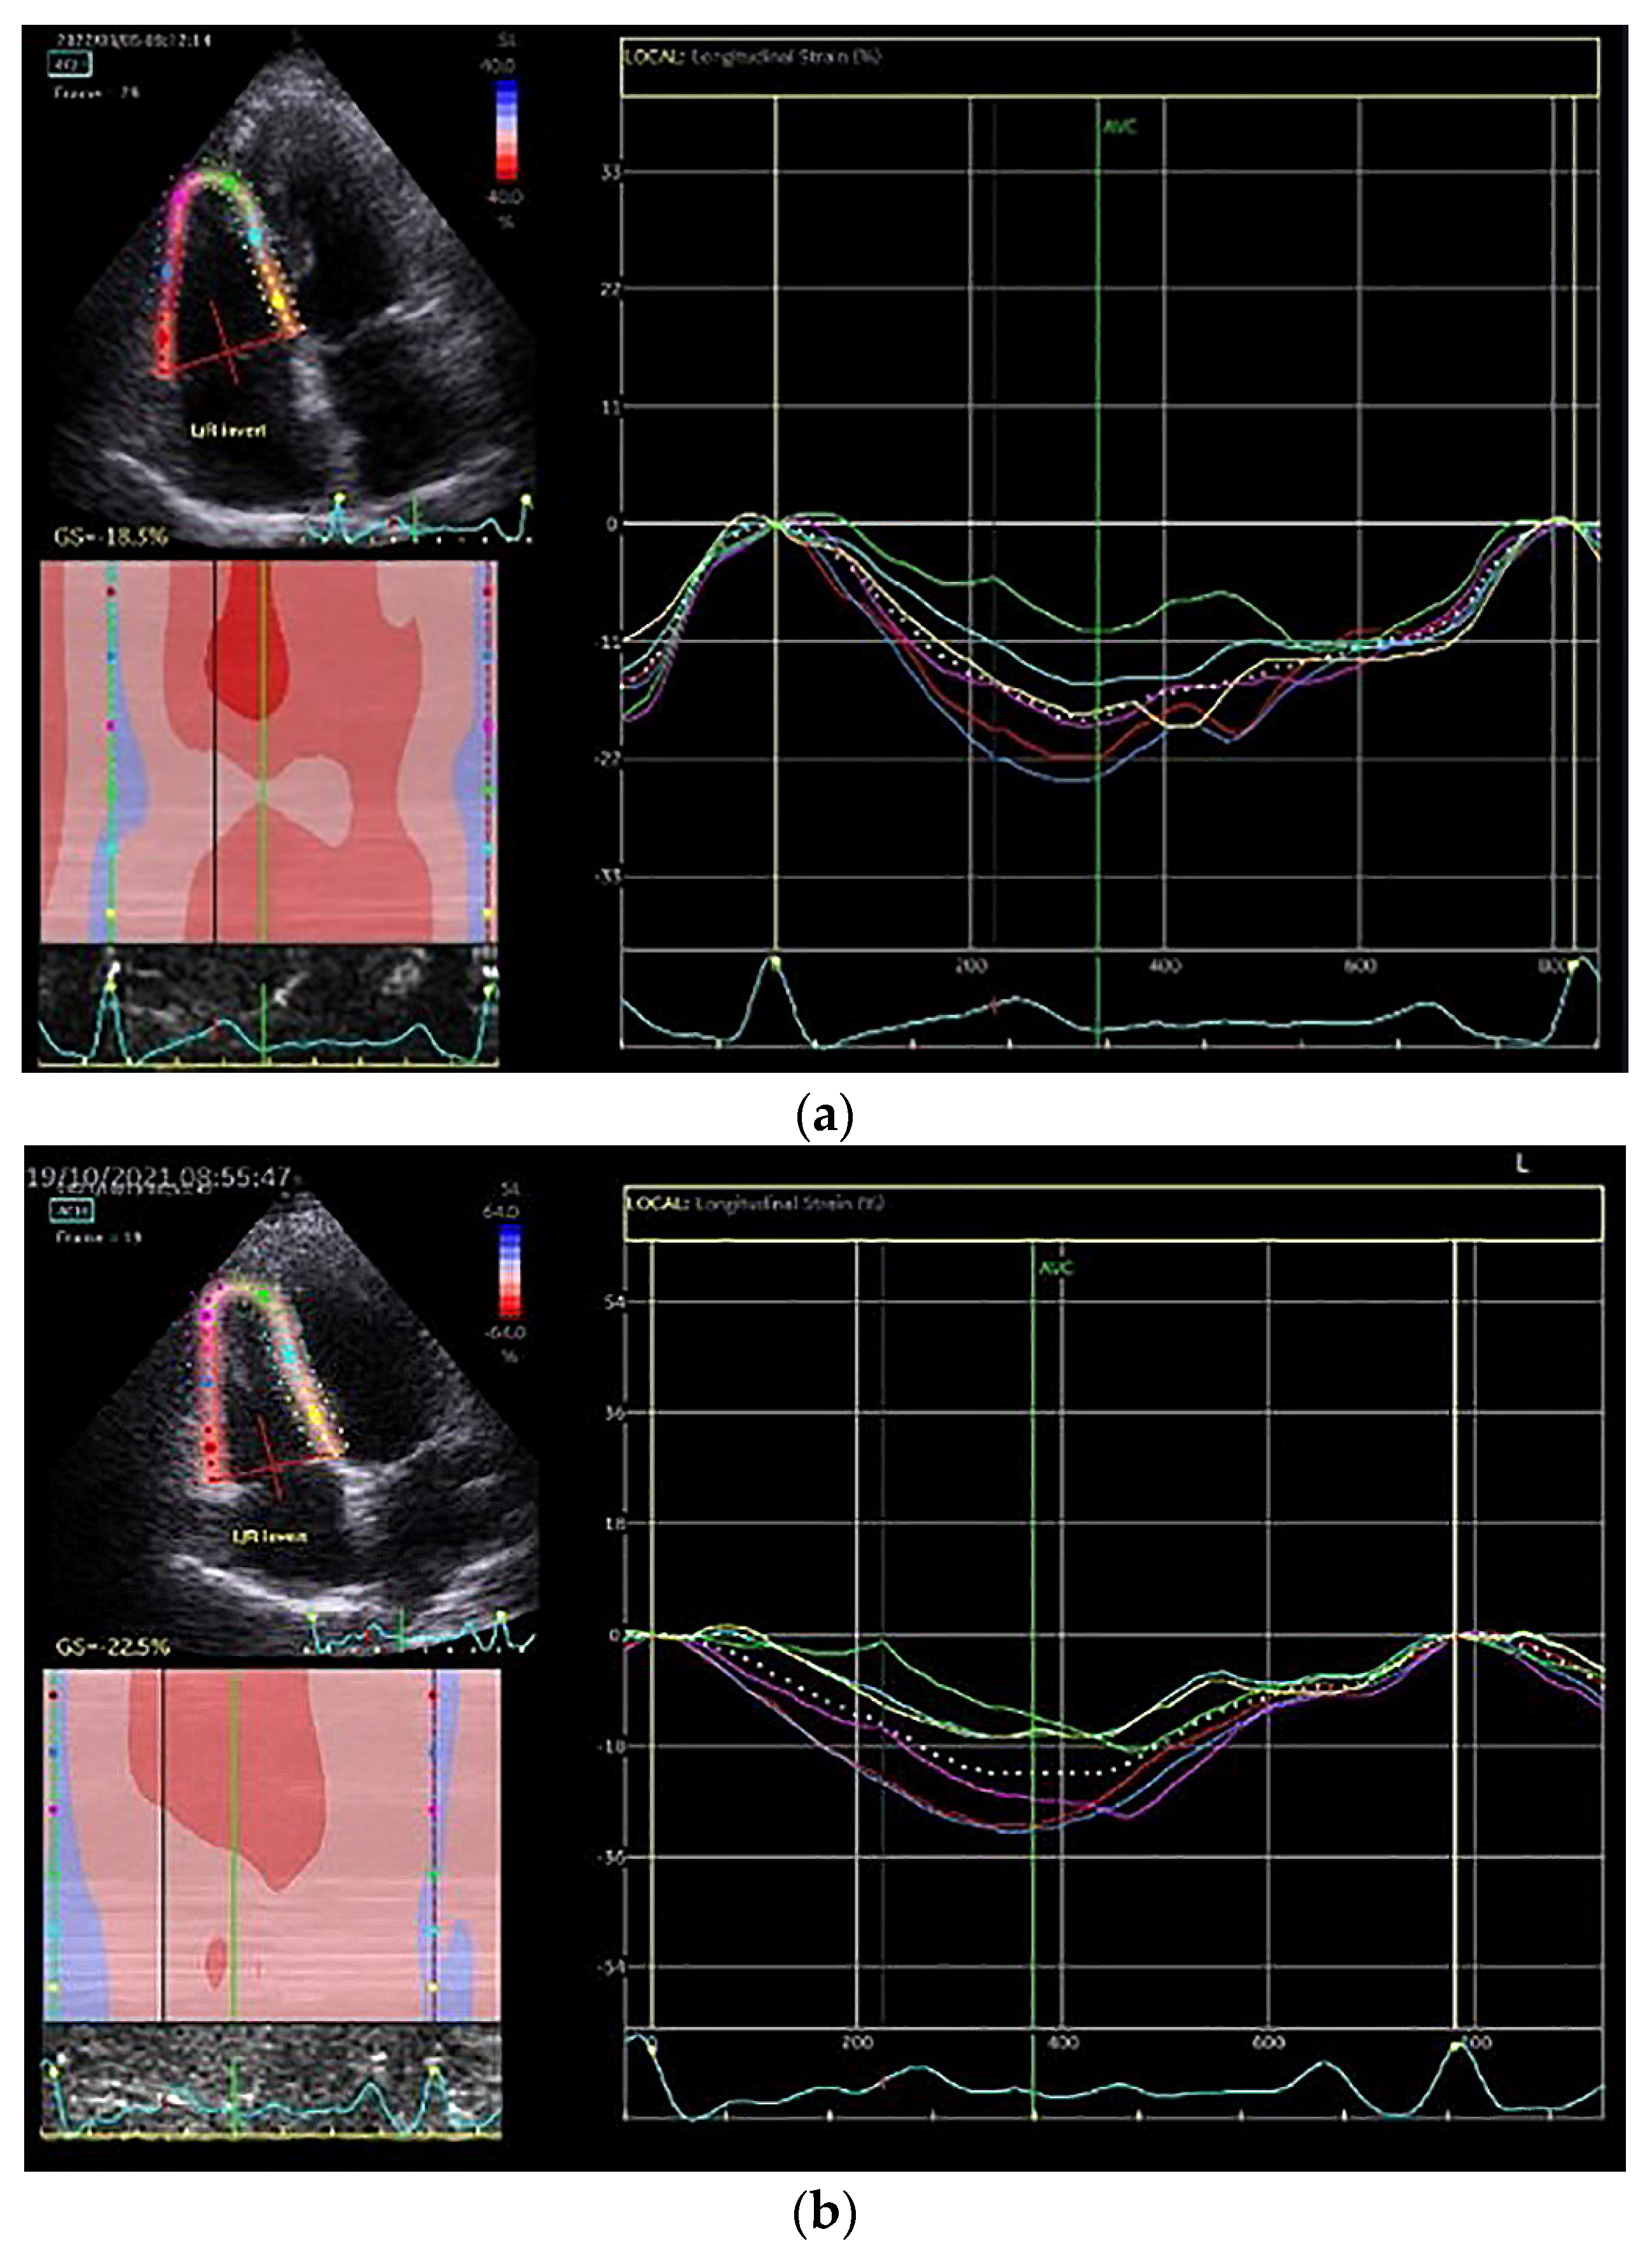

| RVFWLS (%) | −20.9 ± 1.3 | −22.3 ± 2.3 | 0.03 | −21.0 ± 3.4 | −20.7 ± 2.5 | 0.85 | 0.96 | 0.04 |

| RVFWLSbas (%) | −22.2 ± 1.7 | −25.2 ± 2.0 | 0.001 | −21.6 ± 4.1 | −21.6 ± 2.2 | 0.99 | 0.58 | 0.001 |

| RVFWLSmid (%) | −21.7 ± 1.5 | −22.5 ± 2.1 | 0.12 | −21.3 ± 3.7 | −20.6 ± 2.7 | 0.52 | 0.66 | 0.06 |

| RVFWLSap (%) | −18.9 ± 2.9 | −19.1 ± 3.7 | 0.85 | −20.1 ± 3.0 | −20.3 ± 4.0 | 0.91 | 0.36 | 0.43 |

| RV4CLS (%) | −20.7 ± 1.1 | −22.1 ± 2.6 | 0.03 | −20.2 ± 2.7 | −20.5 ± 2.7 | 0.72 | 0.45 | 0.05 |